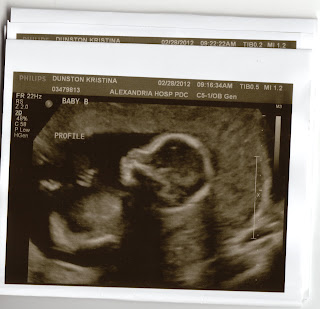

Week 19 and They Are...

Boys! Ryan will be having 2 brothers.

After a lengthy scan today, we found out that both boys are healthy with all of their digits and developing right on track. Baby A currently weighs 10 ounces and Baby B weighs 11 ounces. Mommy will now go back every few weeks to check their growth.